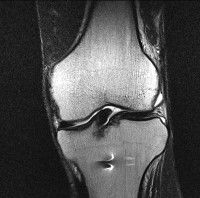

무릎 mri 간단히 봐주실 수 있으시나요 ㅠㅠ

안녕하세요 8년전 십자인대 수술하고 최근 무리한 운동에 무릎 불편감이 생겨서

mri 찍었습니다.

진단결과는 첫 찍은 병원에서 활액막염 이라는 진단을 받았습니다. 혹시 봐주실 수 있으실까요?

올라온 MRI가 단편적이라서 정확한 진단에 어려움이 있지만 십자인대에는 큰 이상이 있지는 않은것 같으며, 무릎관절내 물이 있는 것으로 보아 활액막염의 진단이 맞을 것 같습니다.

하지만 단편적인 영상이기 때문에 촬영병원에서 정확한 판독지 등을 받으시는 것이 좋겠습니다.